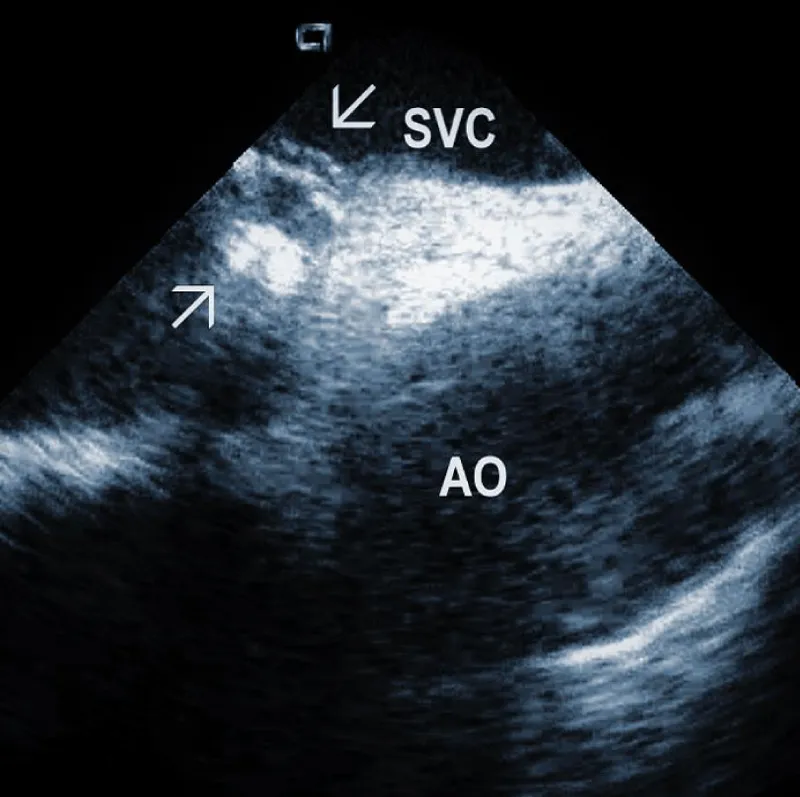

Areas of fibrous adherence: Areas of fibrous adherences or attachments (i.e., scar tissue) can be visualized as echo-dense structures along the lead course (Figure 3A). Multiple leads are usually attached by fibrous tissue together (Figure 3B). The location of fibrous adherence can be anywhere in the course of the lead [7,10]. In a study by Bongiorni, et al. [7], scar tissue was noted by ICE in the subclavian vein, innominate vein, and the right ventricle in about 80%, 68%, and 68% of cases, respectively. Sadek, et al. [10] described attachments less frequently – only in 18/50 pts (36%), predominantly intracardiac. Anecdotal cases were reported on specific locations of adhesions, such as a vulnerable “stalk” attaching the papillary muscle to the RV endocardium [18]. Notably, the fibrous attachment presence correlated with the extraction procedure’s difficulty. These patients were more likely to have a “complex” extraction procedure. Subjects who did not have evidence of lead attachment were less likely to require the advancement of the extraction sheaths past the superior vena cava and less likely to require advanced extraction tools such as snares.

Figure 3A: Fibrous adherences (arrow) attaching the lead within the superior vena cava (SVC). AO: Ascending aorta.

Figure 3B: A convolute of 2 leads attached together with fibrous tissue at the level of tricuspid valve (arrows). RA: Right Atrium; RV: Right Ventricle.